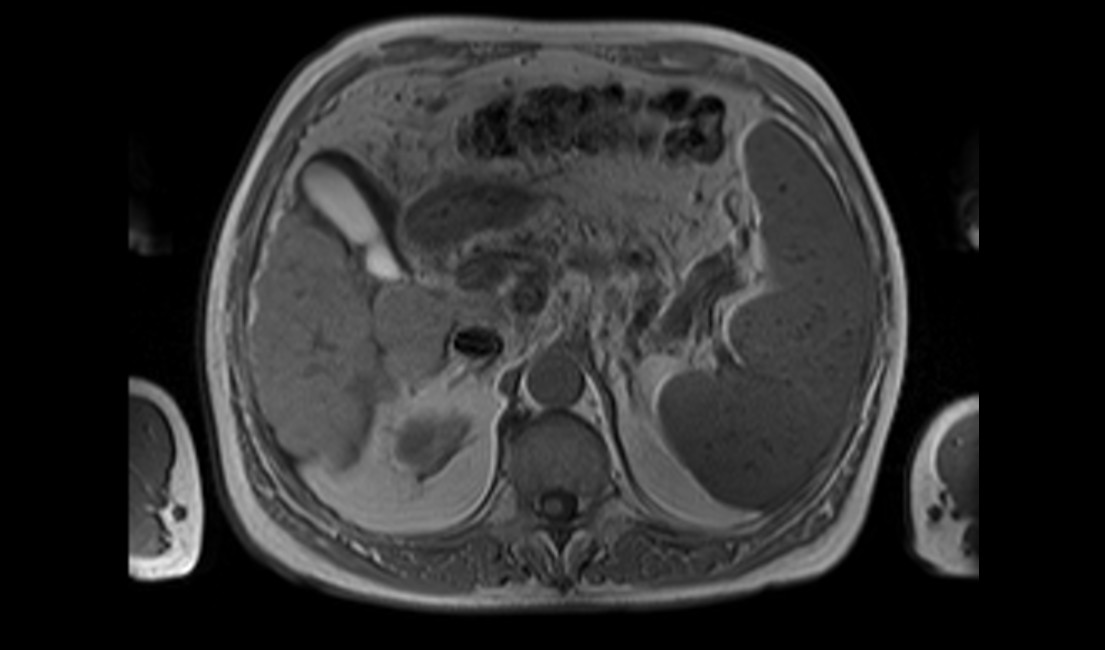

Boricic, Ivan